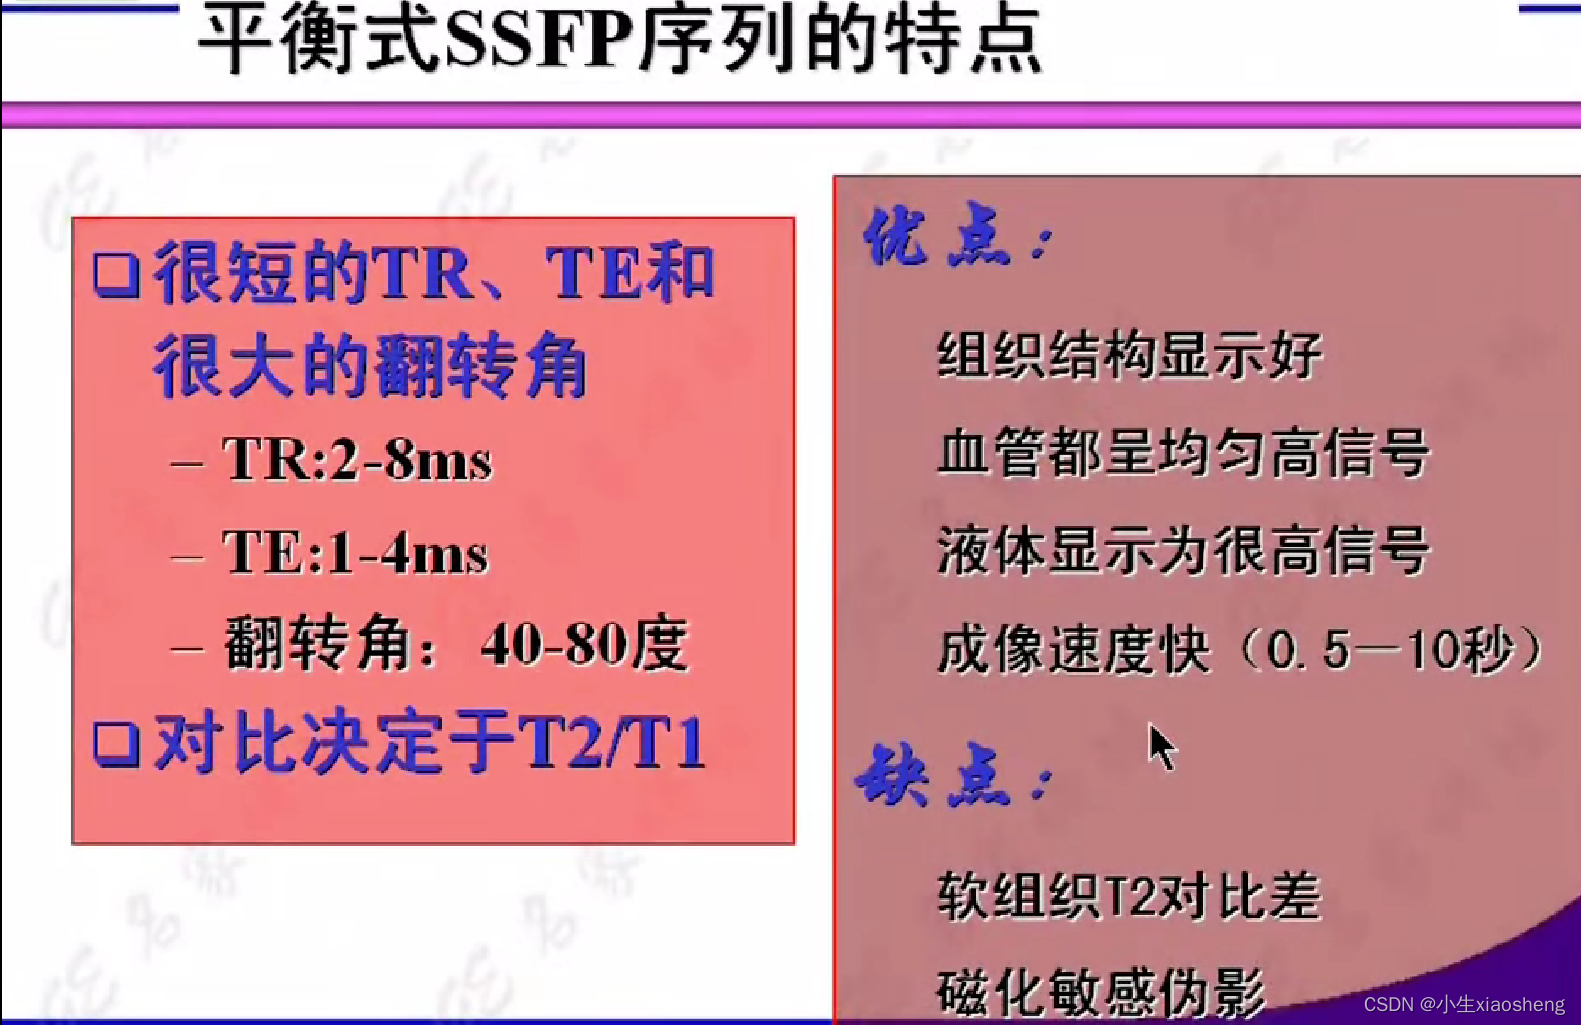

3.平衡SSFP序列

TR和TE要小一点能得到更好的效果图片。